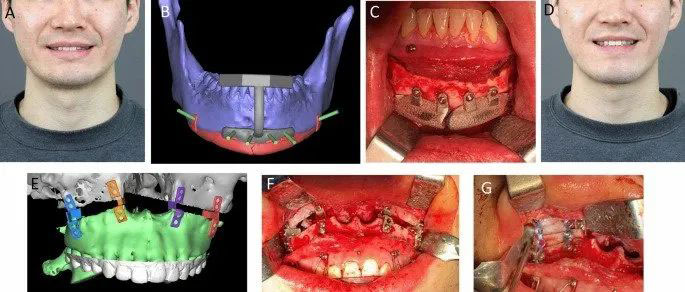

△其中一個修復手術案例研究。圖片來自《Nature》。

該研究記錄的手術中使用的頜面部鈦合金植入物是通過電子束熔化(EBM)和選擇性激光燒結(SLS)工藝3D打印的??偣灿?8個植入物被3D打印出來,然后被插入16名不同患者的上頜骨(面部的主導部分)、下頜骨(下顎)或顴骨(臉頰/乳頭)。

這些病人中,有7名女性和9名男性,年齡從9歲到78歲不等。共對28個缺陷區(qū)域進行了手術,包括5個下頜段、9個顴骨、10個下頜體、角或下巴,以及4個上頜區(qū)域。

然后進行了長期隨訪,每個病人的隨訪時間從8到79個月不等。該研究主要分析了鈦合金種植體的骨融合情況,但也記錄了術后感染、種植體錯位、功能效果、患者滿意度、沉降、種植體周圍的骨溶解以及出現的任何并發(fā)癥。